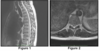

A 16-year-old girl is evaluated for paresthesia in both legs and an unsteady gait. T2-weighted non- contrast sagittal (Figure 1) and axial (Figure 2) MR images are shown. Which of the following is the most likely diagnosis? Answers: A. Cavernous malformation B. Spinal cord infarction C. Glioma D. Ependymoma E. Arteriovenous

Correct Answer: Cavernous malformation